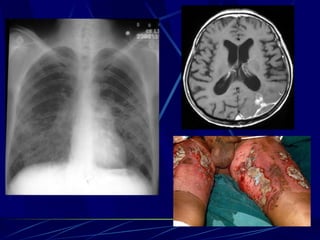

Histoplasma capsulatum Intracelular facultativo en células RES Causan  Neumonía (asintomática usualmente) Hepatoesplenomegalia Lesiones calcificadas Infecciones diseminadas (en SIDA);  lesiones mucocutáneas.

Coccidioides immitis Enfermedad Valley Fever:  neumonia que resuelve, eritema nodoso, artritis Lesiones pulmonares calcifican Sistémica en SIDA:  meningitis, lesiones mucocutáneas. Se diseminan en el 3er trimestre del embarazo!

Blastomyces dermatitidis Enfermedad: Blastomicosis:  neumonia aguda o crónica Se disemina Ya que no resuelven ocasionalmente, se tratan con ketoconazol

Aspergillus fumigatus Enfermedades: Aspergilosis broncopulmonar alérgica Aspergilosis invasiva  Factores: Neutropenia severa, CGD, CF, Quemaduras (Hongo más común) Invade tejidos causando infartos y hemorragea, meningitis, celulitis. Tratamiento:  Amfotericina B

Histoplasma capsulatum Intracelularfacultativo en células RES Causan Neumonía (asintomática usualmente) Hepatoesplenomegalia Lesiones calcificadas Infecciones diseminadas (en SIDA); lesiones mucocutáneas.

Coccidioides immitis EnfermedadValley Fever: neumonia que resuelve, eritema nodoso, artritis Lesiones pulmonares calcifican Sistémica en SIDA: meningitis, lesiones mucocutáneas. Se diseminan en el 3er trimestre del embarazo!

Blastomyces dermatitidis Enfermedad:Blastomicosis: neumonia aguda o crónica Se disemina Ya que no resuelven ocasionalmente, se tratan con ketoconazol

Aspergillus fumigatus Enfermedades:Aspergilosis broncopulmonar alérgica Aspergilosis invasiva Factores: Neutropenia severa, CGD, CF, Quemaduras (Hongo más común) Invade tejidos causando infartos y hemorragea, meningitis, celulitis. Tratamiento: Amfotericina B